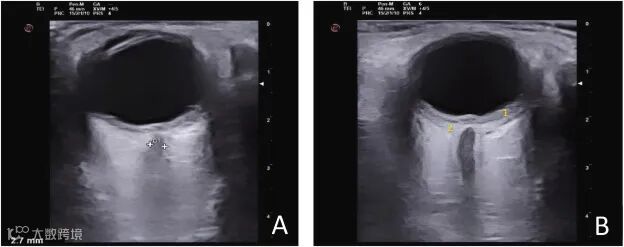

超声检查

急性期B超可见弥漫性脉络膜增厚,伴浆液性视网膜脱离、玻璃体混浊等表现,但一般无玻璃体后脱离。

VKH患者的双眼均存在弥漫性后部脉络膜增厚并伴有视网膜下液。